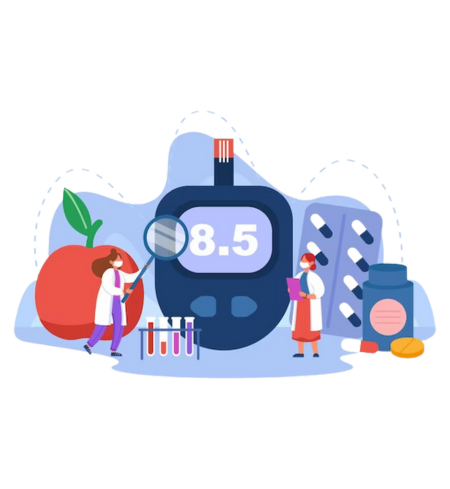

Addressing Diabetic Impotency

Diabetic impotency, often a distressing consequence of diabetes, can significantly impact one's quality of life and intimate relationships. At Dr. Gupta Clinic, we provide comprehensive understanding and effective solutions tailored to address the unique challenges of diabetic impotency. Our specialized approach integrates medical expertise, personalized care, and supportive guidance to help individuals regain confidence, restore intimacy, and manage diabetes-related sexual health concerns effectively. Take the first step towards reclaiming your vitality and well-being with our compassionate support and proven treatments.